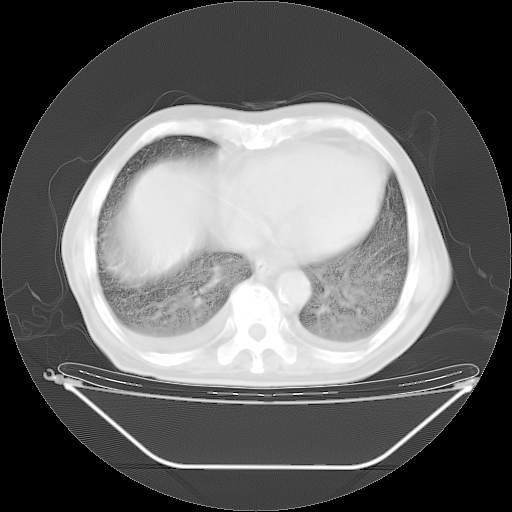

今天复查肺部CT,发现双肺广泛磨玻璃样改变。所以我把3月19日和5月9日相隔50天的肺部CT上传。请大家会诊。

2009年3月19日肺部CT片。

5月9日肺部CT(在4月27日齐鲁医院肺部CT描述部分肺组织磨玻璃样改变,12天后肺组织广泛磨玻璃样改变)